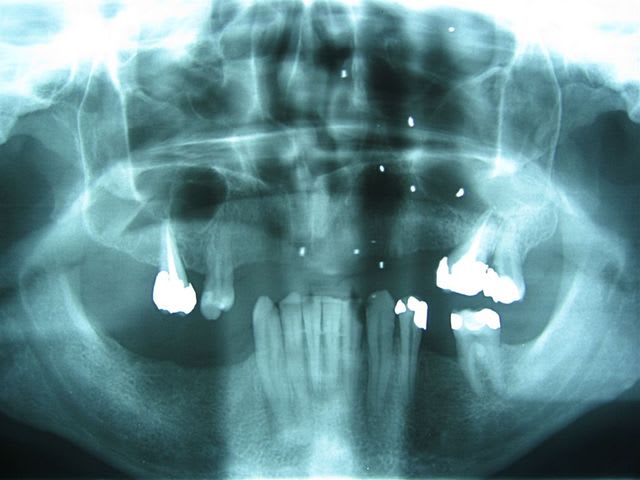

24/03/2007 à 11h32

... il a 27 ans.

c'est toi qui t'y colles?

... on fait ça à plusieurs: ortho, stomato, implanto peut-être.

Le gosse a l'air motivé.

la chevauchée fantastique!